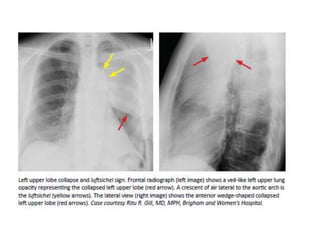

COLLAPSE

• Direct signs of atelectasis are from lobar volume loss

and include:

-Displacement of the fissures

-Vascular crowding.

• Indirect signs of atelectasis are due to the effect of

volume loss on adjacent structures

-Elevation of the diaphragm.

-Rib crowding on the side with volume loss.

-Mediastinal shift to the side with volume loss.

-Overinflation of adjacent or c/l lobes

-hilar displacement

COLLAPSE • Direct signsof atelectasis are from lobar volume loss and include: -Displacement of the fissures -Vascular crowding. • Indirect signs of atelectasis are due to the effect of volume loss on adjacent structures -Elevation of the diaphragm. -Rib crowding on the side with volume loss. -Mediastinal shift to the side with volume loss. -Overinflation of adjacent or c/l lobes -hilar displacement